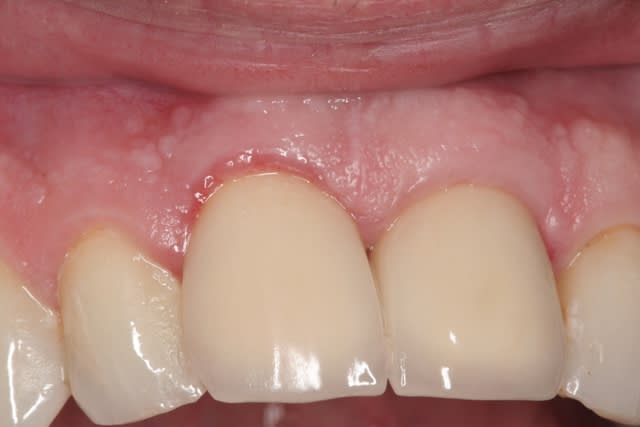

le hasard fait parfois bien les choses...patient revu ce matin pour une "bricole" sur une restauration postérieure...

il est intéressant de voir la maturation des tissus mous...et en plus VS des différences au niveau de l'hygiène, pas mal secteur 2 mais perfectible secteur 1...

ici on est à 3 mois post pose prothèses d'usage...la photo, prise un peu décalée, donne l'impression d'une différence de hauteur des collets, mais il n'en est rien (ou alors très peu...)

quand même content du résultat...;-) même si j'ai (lourdement)insisté pour que l'hygiène soit un peu mieux suivie...

Img 3108 haqvx5 - Eugenol